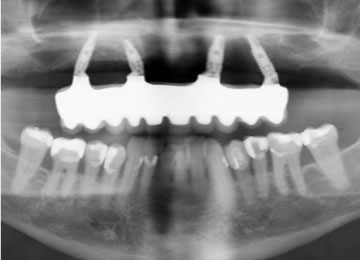

Имплантация зубов: фото «До» и «После»

All-on-4

All-on-6